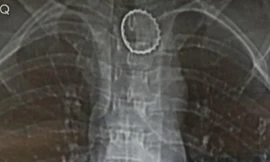

TPO - Trong lúc uống nước ngọt, nam bệnh nhân đã vô tình nuốt luôn cả nắp chai. 2 tháng sau, bệnh nhân bị đau tức ngực, khó thở. Khi đến bệnh viện kiểm tra, bác sĩ phát hiện chiếc nắp chai có hình răng cưa đang nằm trong thực quản người bệnh.